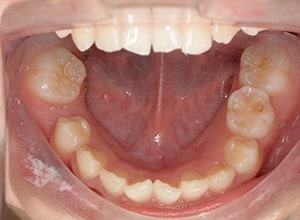

| 主訴 | 右下6近心傾斜、上顎前歯のでこぼこ | 診断名 | 下顎右側第一大臼歯近心傾斜、 上顎左側第一大臼歯近心傾斜症例 |

| 初診時年齢 | 11歳6ヵ月 | 性別 | 女 | 動的治療期間 | 5ヵ月 | ||

| 口腔内所見 | over jet 3.5mm,over bite4.0mm、下顎正中右側偏位2.0mm、大臼歯関係は左側Ⅰ級であったが、右下6は右下E早期喪失のため近心傾斜しておりⅢ級の臼歯関係となっていた。また上下顎前歯は軽度の叢生を呈していた。 |

| パノラマ所見 | 右下5は右下6近心傾斜により萌出部位不足が認められた。上下顎8歯胚が確認できた。 |